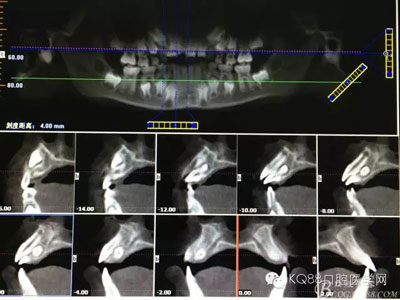

患者、孫xx、男、10歲。主訴:上前牙排列不齊,要求治療。??茩z查:11與21之間有間隙約3mm,11唇側(cè)傾斜,12位于11是腭側(cè)萌出,11與12完全唇腭向重疊。cbct檢查:11與21之間有一倒置多生牙,多生牙牙根位于11與21之間,牙冠位于11與12之間。診斷:埋伏倒置多生牙。治療建議:1.建議拔除倒置多生牙。2.多生牙拔除后,建議早期正畸治療?;颊咄馐中g(shù)方案,簽知情同意書(shū)。

圖3.根據(jù)臨床檢查,做CBCT影像檢查:11與21之間有一倒置多生牙,多生牙牙根位于11與21之間,牙冠位于11與12之間。

圖3.水平方向觀察多生牙與11和12之間的關(guān)系:多生牙牙冠緊鄰11與12牙根。